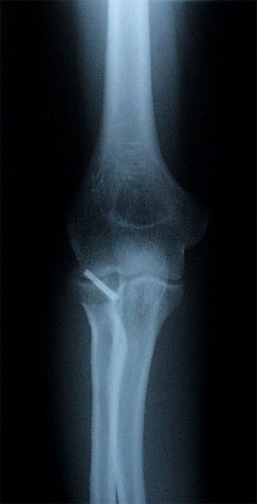

Straight Elbow I was awake during my elbow surgery, which was weird since I could hear Dr. Howson and her assistant debating about what size of screw to use, worrying about the pins slipping, and tapping at things with what sounded like a little hammer. (The pins were plastic and will disintegrate, but the screw will be with me forever.)

Bent Elbow